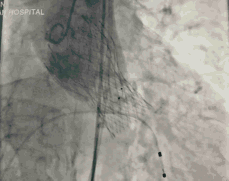

葛均波院士、周达新教授结构团队对这位生物瓣衰败的老年男性患者行瓣中瓣植入术,术中选择了23mm VenusA-Valve(杭州启明),植入过程顺利,术后冠脉无堵塞,未出现瓣周漏,术后跨瓣压差接近于0,赢得了参会专家的激烈掌声。

此患者是我国第一例接受TAVR患者,十年后再次接受TAVR,并获得完美结果,意义重大。本病例也是我国第一例TAVR瓣膜衰败患者再次TAVR手术的病例。

本病例的成功也为目前接受TAVR患者远期瓣膜衰败问题的解决提供良好借鉴,为这些患者解除后顾之忧。

图5 TAVR瓣膜释放后